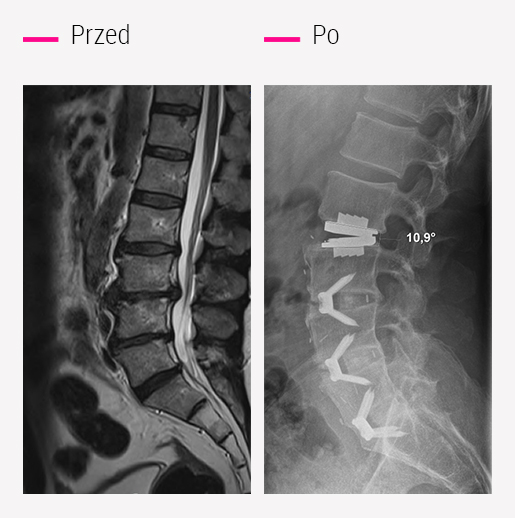

Prodisc®

Implant zastępujący dysk nr 1 na świecie od ponad 20 lat, opatentowany przez CCV Montpellier.

Proteza Prodisc®jest opatentowaną technologią chirurgicznej wymiany dysku o udowodnionym działaniu pomagającym utrzymać równowagę i ruch kręgosłupa, spowolnić zużycie sąsiednich dysków i przyspieszyć powrót do aktywności.